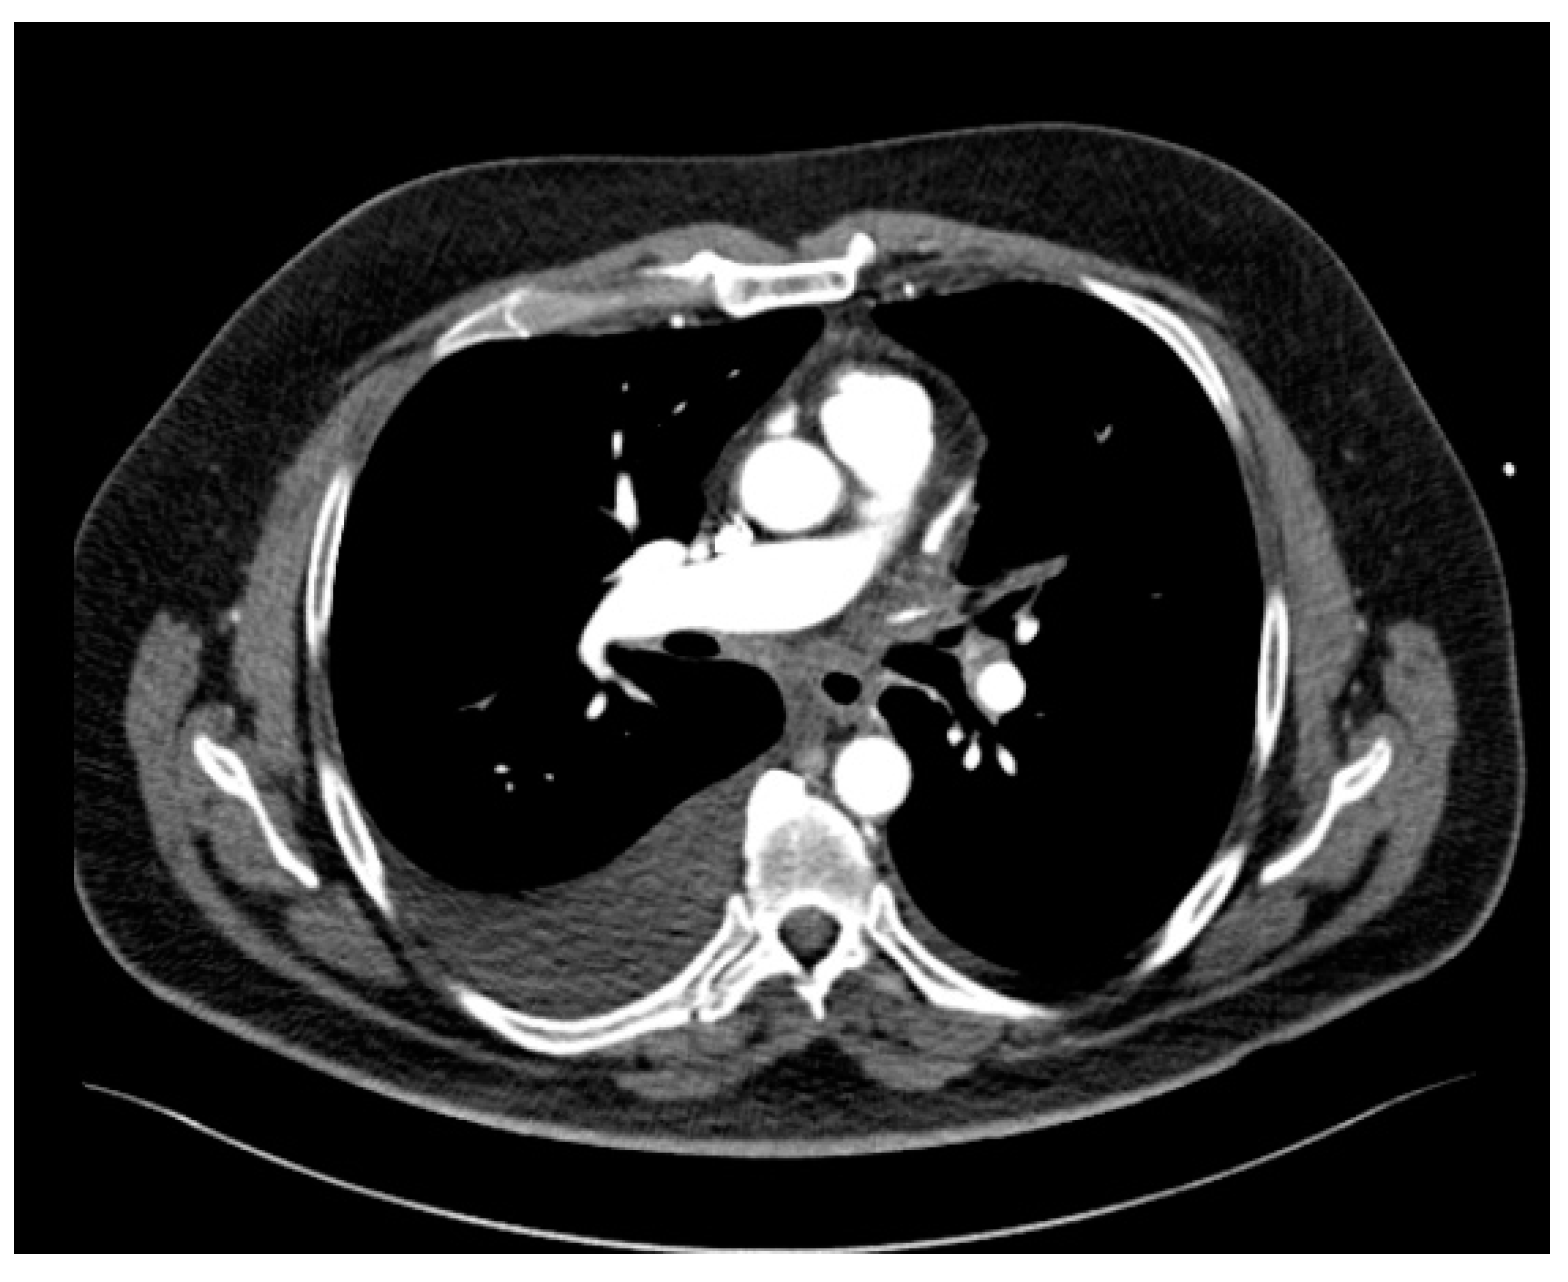

The CT study revealed stenosis of all four pulmonary veins (severe stenosis of the right superior, right inferior and left inferior PVs, near-occlusion of the left superior PV and of the vein draining the apical segment of the right lower lobe) (Figure 2).

Figure 2.

Cardiac CT angiography revealing stenosis of all four pulmonary veins: (a) maximum intensity projection (MIP) reconstruction; (b) volume rendering technique (VRT) reconstruction.

The patient also presented bilateral pleural effusion (40 mm on the right side and 7 mm on the left side) and a soft tissue attenuation obliterating normal mediastinal fat planes and encasing both the PVs and the esophagus posterior to the left atrium, an aspect suggesting fibrosing mediastinitis probably caused by the severe inflammation induced by radiofrequency ablation associated thermal injury (Figure 3). As for the parenchymal findings, a global mosaic attenuation was present, especially in the right middle lobe, together with a ground-glass opacity in the apical segment of the left lower lobe. The parenchymal findings were mostly consistent with pulmonary veno-oclusive disease and an area of hemorrhagic infarction.